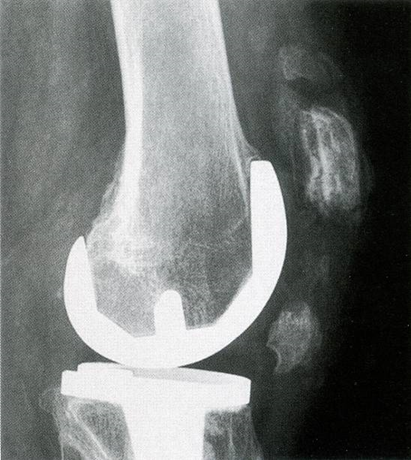

在膝关节翻修术中,部分限制型假体适用于通过软组织松解等手段能获得膝关节伸屈间隙和内外侧平衡、骨缺失不明显、骨质较好时。

胫骨侧加粗加高的中央柱和股骨侧加宽加深的髁间凹槽相匹配,控制内外翻稳定,可部分代偿侧副韧带功能

常用于存在骨缺损和关节不稳的翻修手术

建议加用髓内柄以获得更高的稳定性